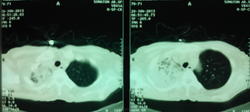

провели кт: заключение по КТ ОГК - картина деструктивной полисегментарной пневмонии правого легкого, и сегментарной нижней доли левого, КТ ОБП - картина жировой дистрофии печени, киста левой почки. Сами снимки мне увидеть не удалось - родственники зачем то увезли в деревню, надеюсь привезут на днях и я хотя бы их сфотографирую для вас.

перестала самостоятельно ходить, возят ее на кресле, а ведь еще неделю назад сама приходила на R графию, теперь стоит при поддержке других. внешне опять таки никаких проявлений - разве только вялой стала.

если кому еще интересно, ее перевели в реанимацию, динамика отрицательная, КТ я от ее родственников так и недождался, лечащему врачу дал рекомендации чтоб провели R-контроль, посмотрим.